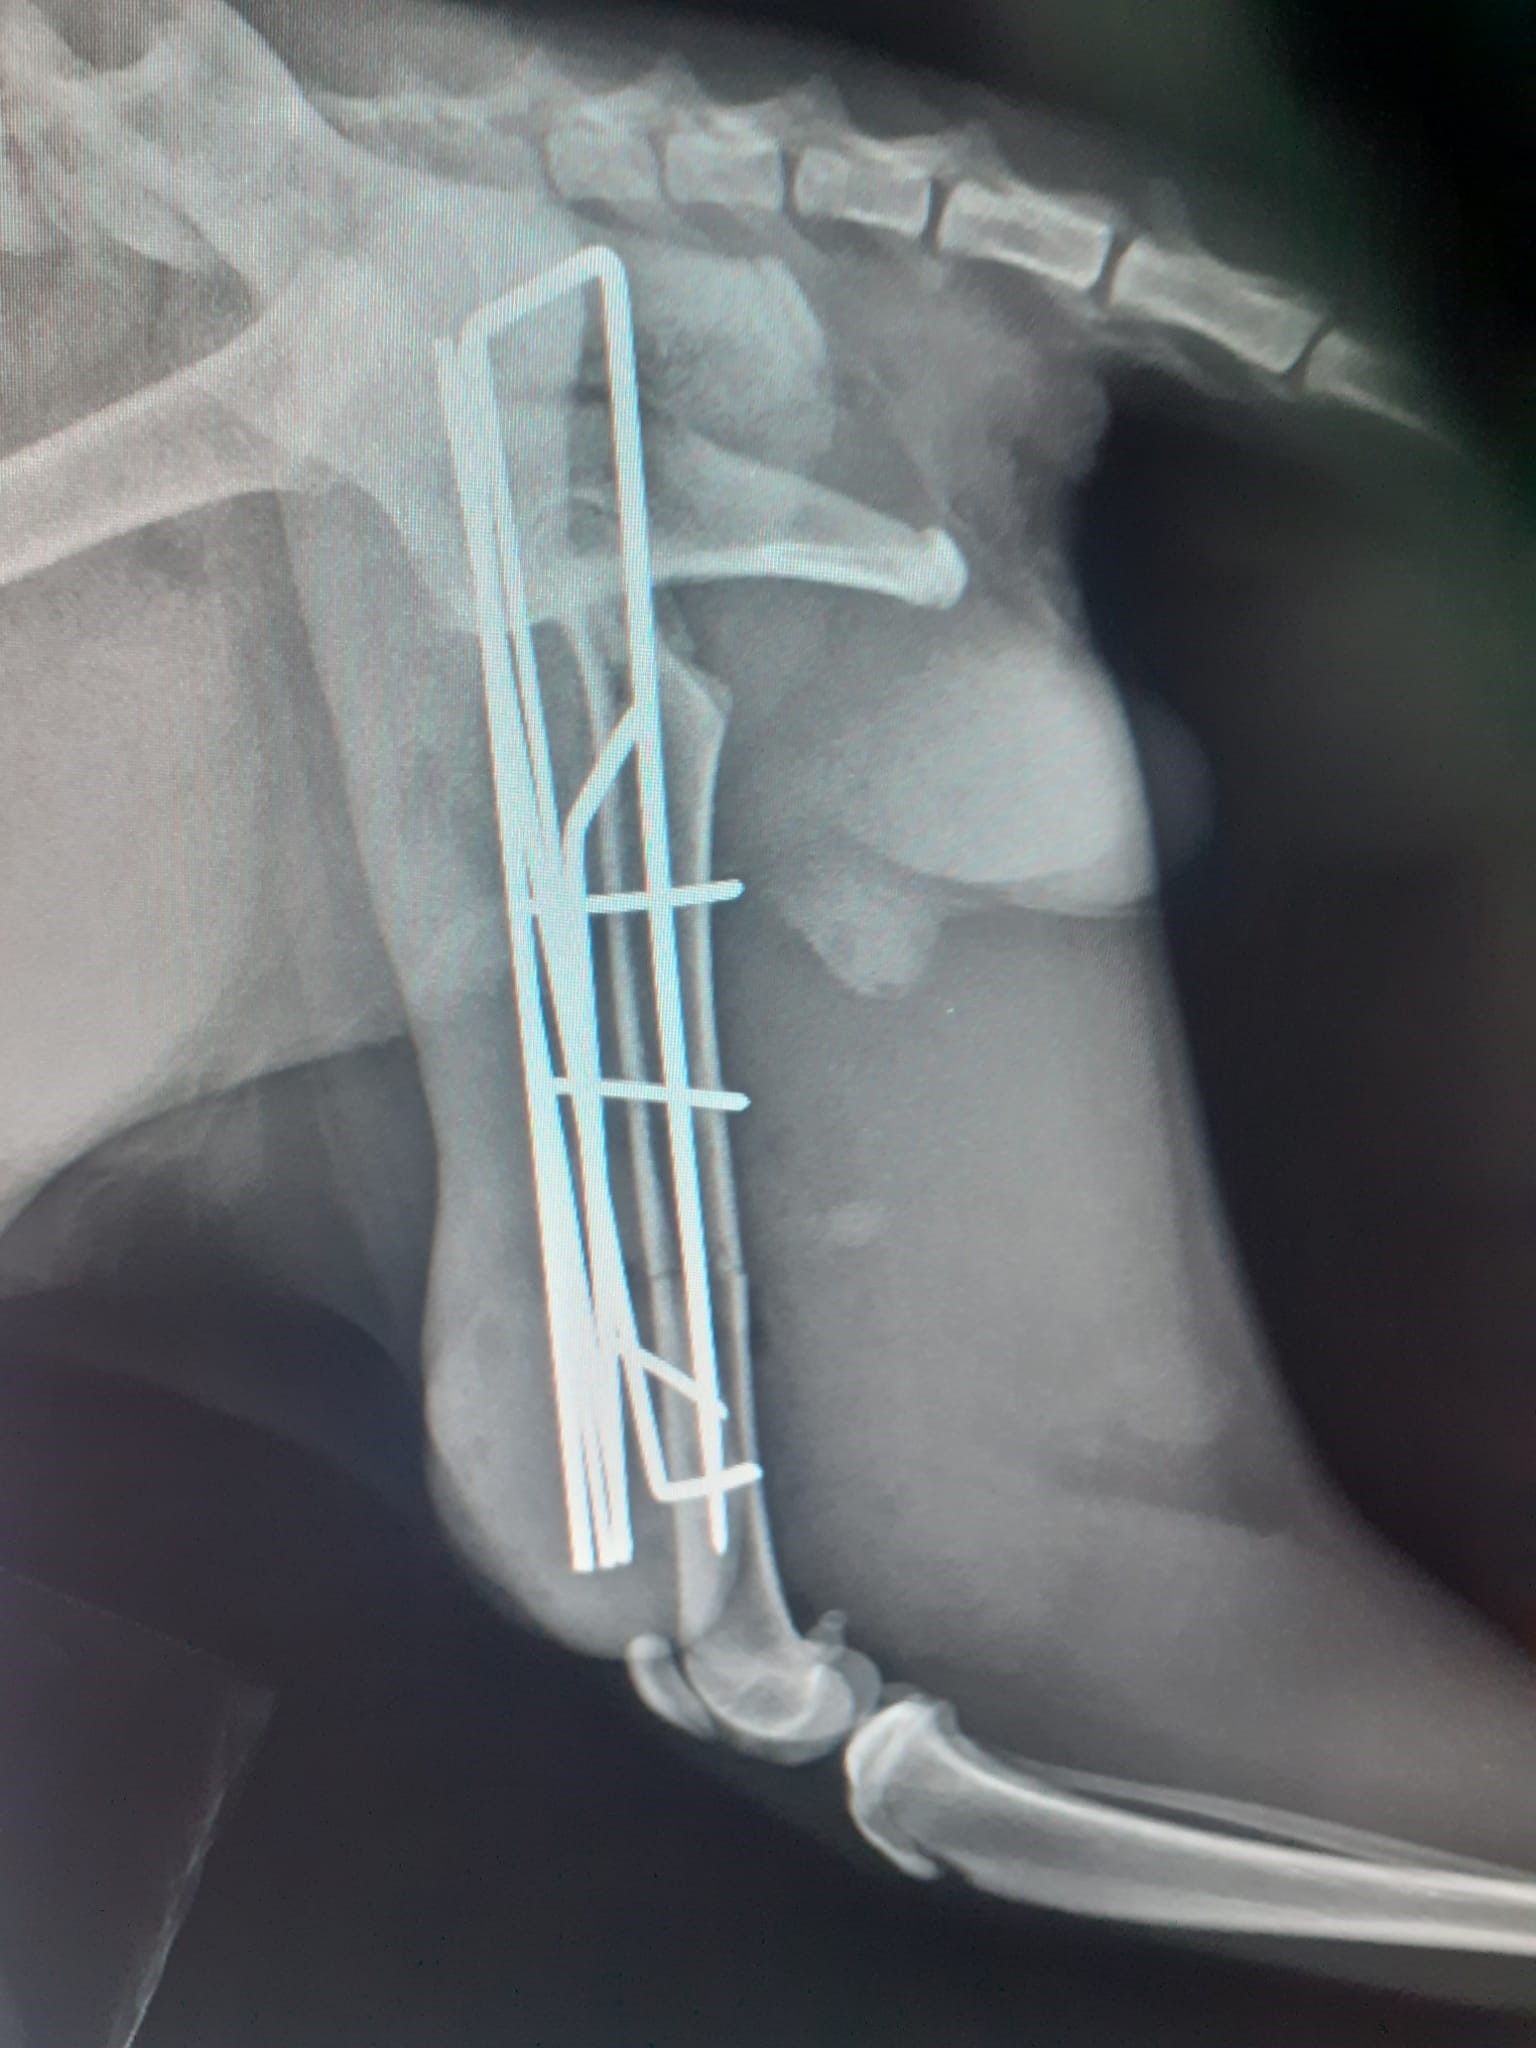

Alla clinica veterinaria Città di Catanzaro siamo a disposizione per eseguire controlli radiografici specifici per la diagnosi di alcune tra le più diffuse malattie ortopediche che affliggono molte razze canine, soprattutto nella fase della crescita.

Con sicurezza ed efficacia, i nostri esperti di ortopedia veterinaria sono capaci di prevenire e curare tutti i tipi di problematiche relative all'apparato muscolo scheletrico, come la displasia dell’anca e del gomito.

In più, la nostra équipe si compone di esperti traumatologi che si dedicano alla diagnosi, al trattamento e alla prevenzione di un ampio spettro di patologie dell'apparato locomotore.

Infine, grazie alla chirurgia ortopedica, è possibile velocizzare la guarigione di tutti quegli animali che hanno subito fratture ossee in seguito a qualsiasi tipologia di incidente.